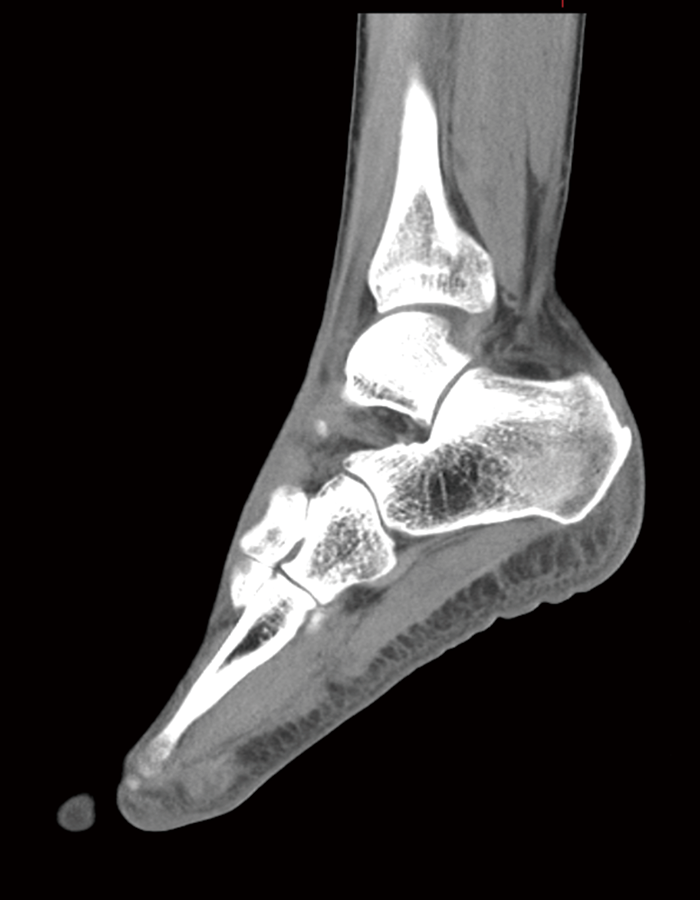

a

踵骨 Dual Energy撮影 骨条件

b

踵骨 Dual Energy撮影 VNCa

図1 踵骨 Dual Energy撮影

a:骨条件 b:VNCa

VNCa画像では骨折が確認できる。